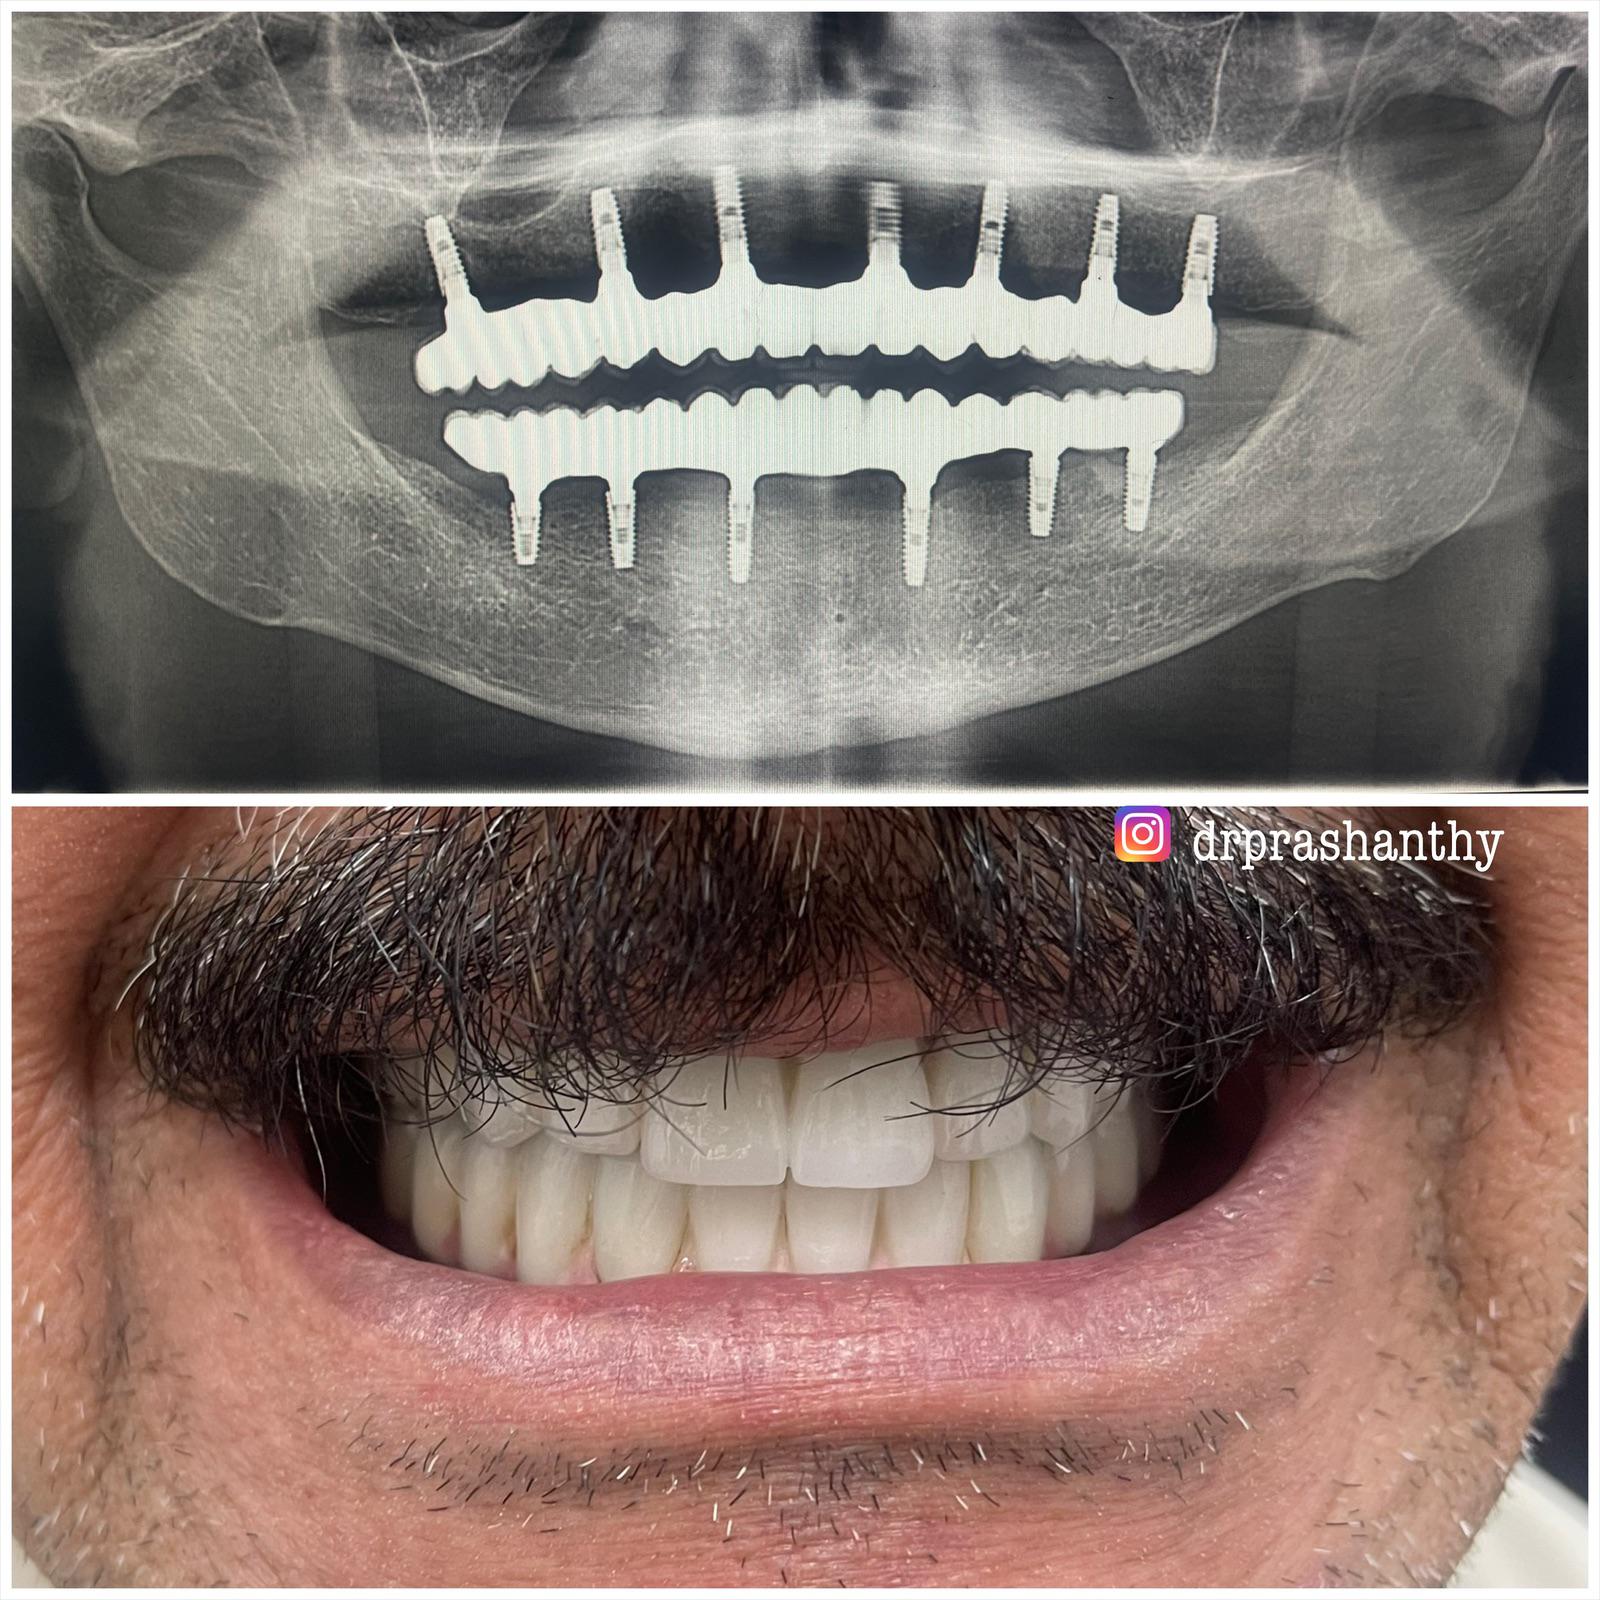

Dr. PRASHANTHY.R.BDS, MDS, FICOI,DICOIPeriodontist / Implantologist-Board certified Diplomate (ICOI )Healthy Gums and Teeth for a Beautiful Smile

Specialist inImplantology